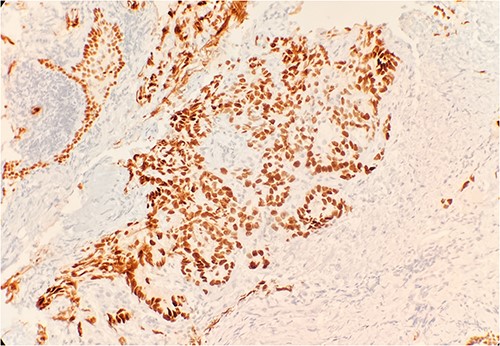

Pathology evaluation from the right middle lobe biopsy showed few clusters of malignant cells, consistent with ADC (Fig. 1). Immunohistochemical staining showed tumor cells were positive for AE1/3, Napsin A and TTF1 (Fig. 2), with ⁓60% Ki-67 positivity. Tumor cells were also negative for CK7 (Fig. 3), p40, p63, CK20 and CK5/6. The overall tumor morphology features and immunoprofile favored moderately differentiated ADC of the lung. However, other primary sites could not be ruled out.

Tumor cells are positive for TTF1 by immunohistochemical stain (IHC) 20×.